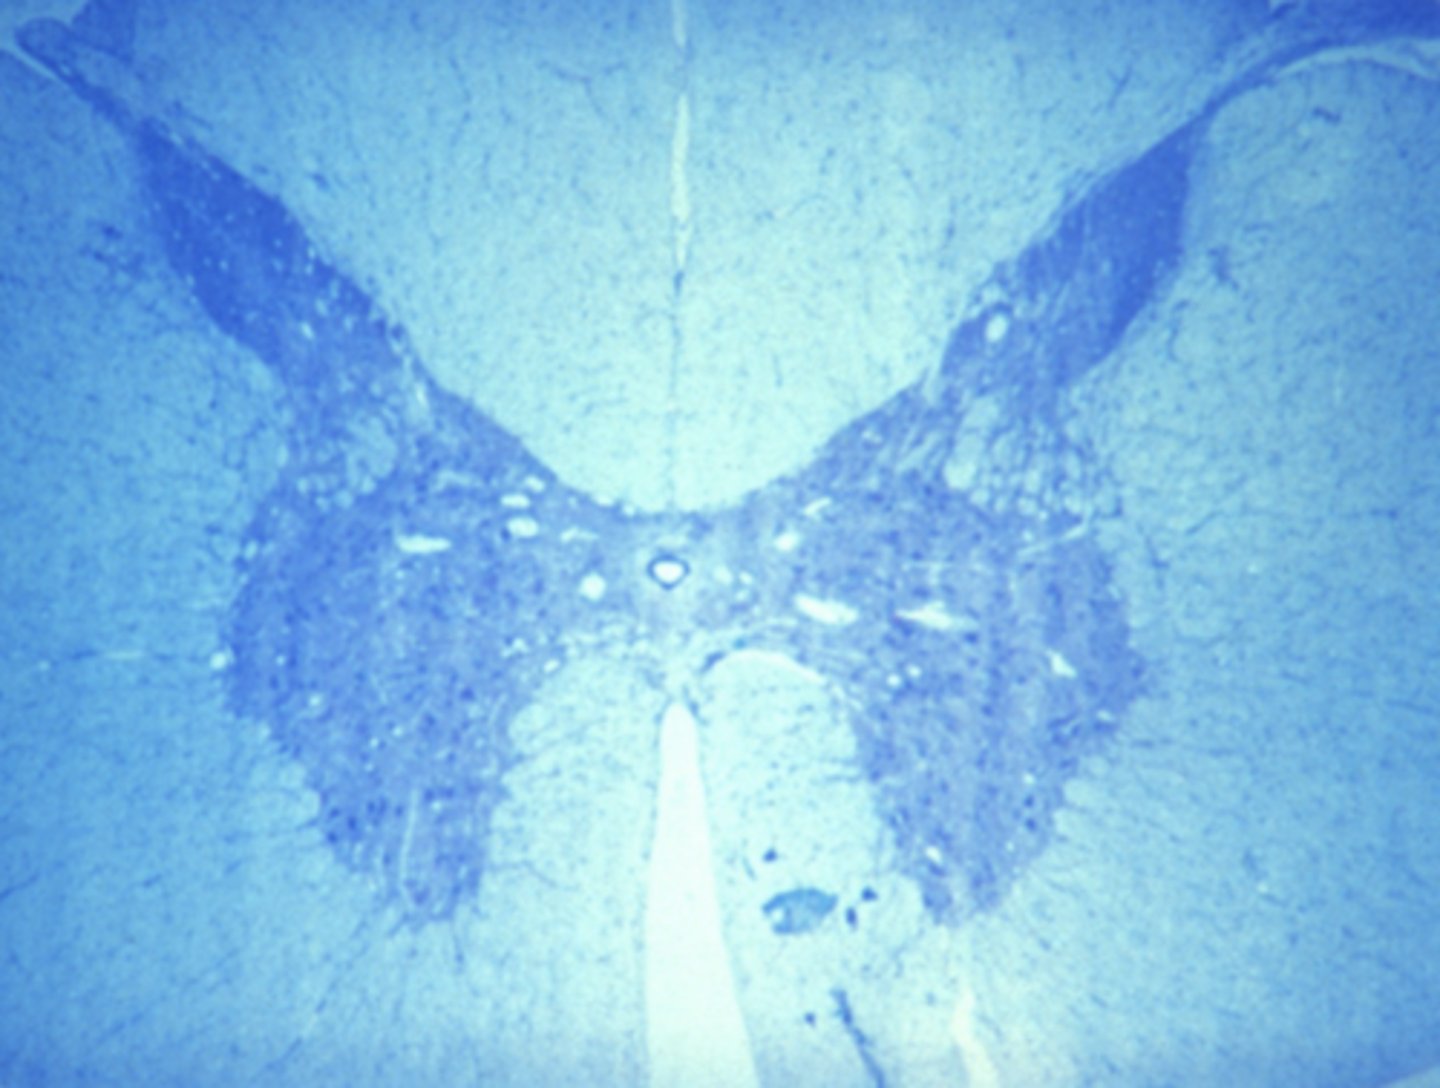

nervous tissue

Which of the four major tissue types is presented in the following image of the spinal cord:

Which of the four major tissue types is presented in the following image of the spinal cord:

Cells conduct electrochemical impulses

Which is a characteristic of the tissue type in the previous image (nervous tissue):

Cells have an apical and basolateral surface

Cells conduct electrochemical impulses

Cells are contractile

Cells produce an extracellular matrix